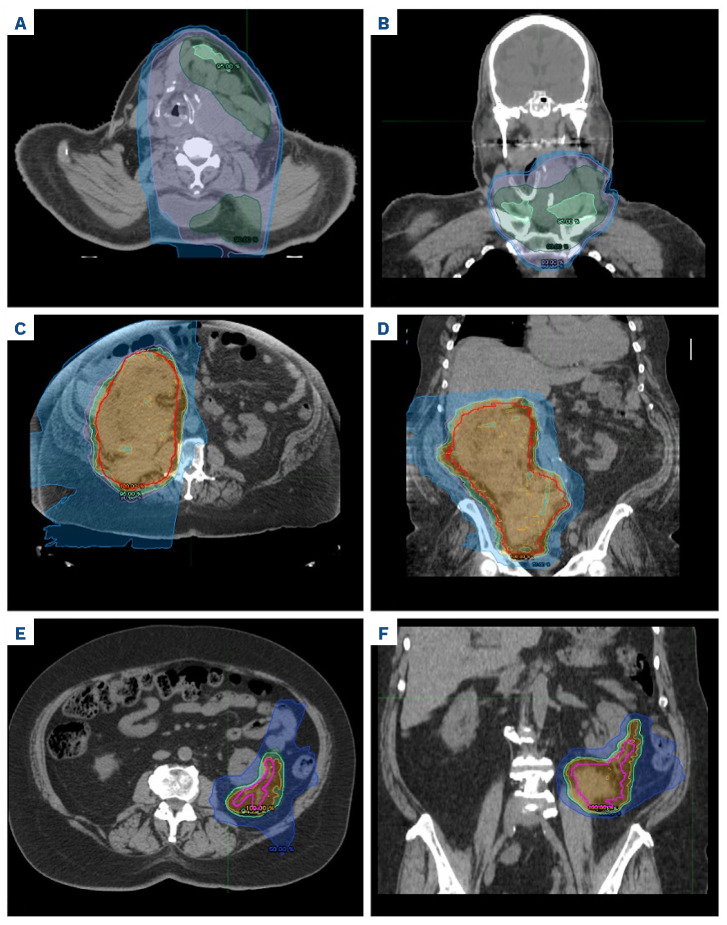

Radiation therapy to manage isolated relapse after chimeric antigen receptor T-cell therapy in multiple myeloma.